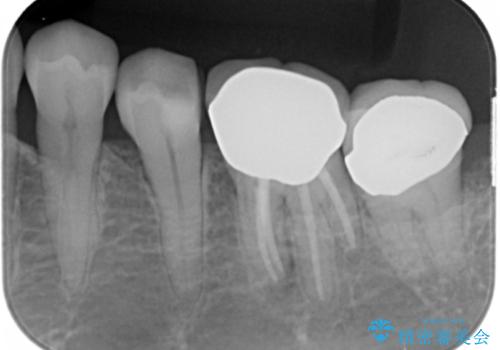

- 詰め物の境目が黒いことを気にされ、来院された患者様です。

精査したところ、左下の奥歯(左下5)のプラスチックの詰め物と歯の境目が虫歯になり、黒くなっていました。

古い詰め物とう蝕を除去し、審美的で適合が良く二次う蝕になりにくいセラミックインレーによる修復を行いました。